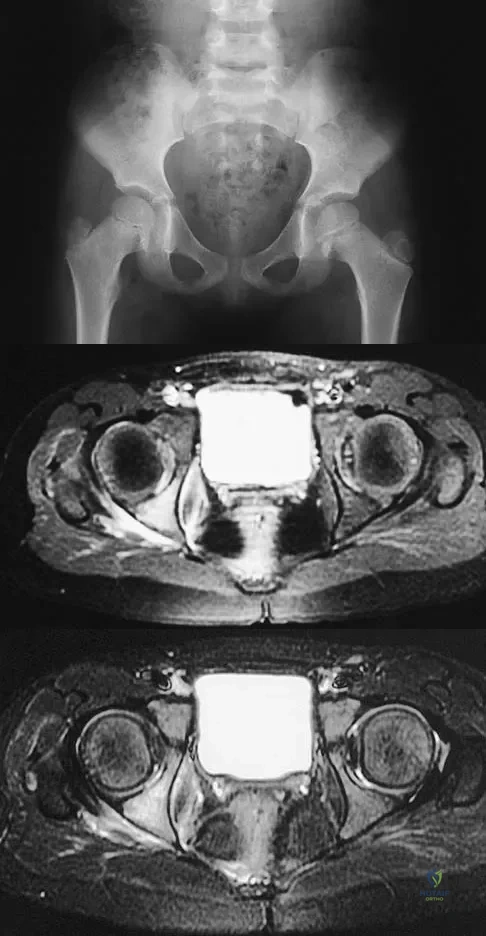

Question 71High Yield

A 5-year-old girl has had a low-grade fever, right hip and buttock pain, and a right-sided limp for the past 5 days. Examination shows diffuse tenderness and extreme pain on range of motion of the hip. Laboratory studies show a peripheral WBC count of 13,500/mm3 and an erythrocyte sedimentation rate of 55 mm/h. A radiograph is shown in Figure 46a, and an axial postgadolinium T1-weighted MRI scan with fat suppression and an axial T2-weighted fast spin echo MRI scan are shown in Figures 46b and 46c. What is the most likely diagnosis?

Explanation